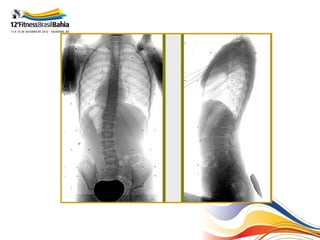

Aspectos Radiológicos

• Topografia;

• Ângulo de Cobb;

• Rotação:

– Nash-Moe

– Perdriolle

• Bending – test;

Grau de Risser

Eixo de referência

Ângulo de Cobb